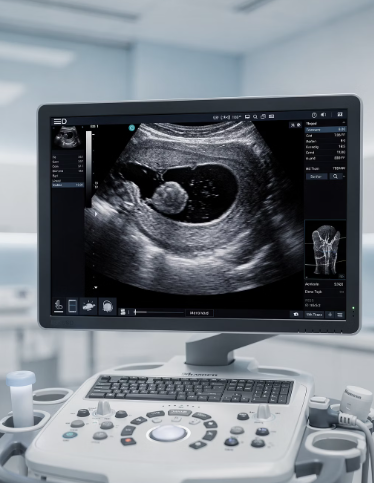

가장 기본이 되는 검사는 경부 초음파 검사예요. 이 검사로 결절의 크기, 개수, 내부 구성(고형/낭성), 혈류 양상 등을 확인해요. 초음파 결과에 따라 필요시 세침흡인세포검사(FNA)라는 조직 검사를 하게 되는데, 이 과정을 통해 악성 여부를 판별할 수 있어요.